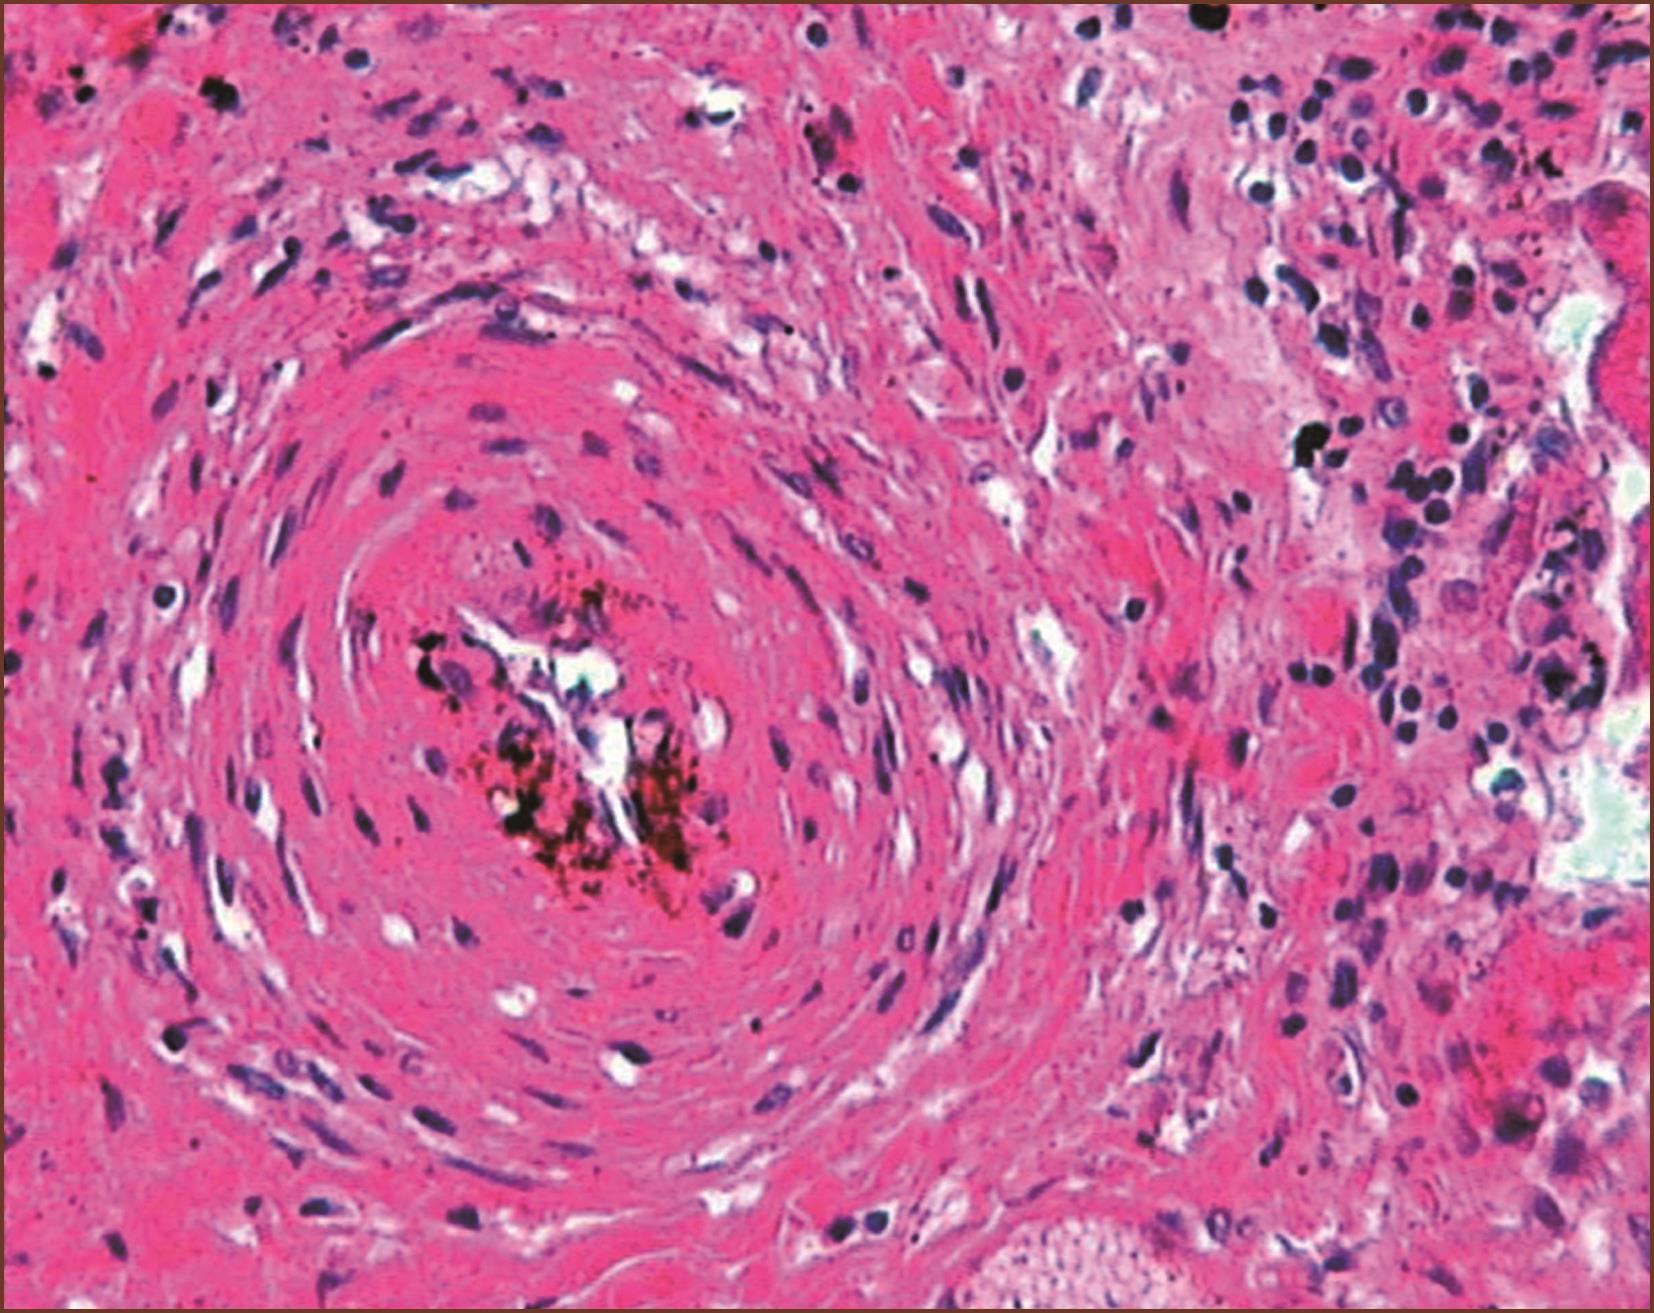

3.丛源性肺动脉病

在大多数严重的PAH,肌型肺动脉和肺微细动脉可发生纤维素样坏死(图3-1-10,图3-1-11)。坏死通常是节段性的,可发展成为动脉瘤样破裂,伴发间质或肺泡腔内出血,最终含铁血黄素沉积。局部修复性的重建血管瘤样的结构就是丛状病变(plexiform)。丛状病变是Ⅳ级肺动脉高压的标志。

丛状病变组织学显示由无规律生长的内皮细胞团(丛)状增生(有作者认为是肿瘤性内皮细胞增生)(图3-1-12,图3-1-13)。丛状病变组成成分有新生内皮细胞团(丛),混杂有肌纤维母细胞、平滑肌细胞和结缔组织基质,形成灶性薄壁的多个毛细血管裂隙。丛状病变的内皮细胞可被血管内皮生长因子(VEGF)和它的受体标记;用α-SM-Actin可以标记丛状病变内的肌纤维母细胞。有的作者形容丛状病变为血管球样生长。有时,丛状病变的管腔宽大,病变类似动静脉畸形。如果管腔内含有纤维素,要与机化血栓进行鉴别。在临床PAH中,丛状病变在肺活检组织中不易见到。在重症PAH一张组织切片上能见到一两处丛状病变,因此至少应该检查10个肺组织块,才能够除外丛状病变。有研究报道,特发性肺动脉高压的丛状病变为单克隆来源;反之在继发性肺动脉高压的丛状病变是多克隆来源。

丛状病变可见在肺小动脉腔内(见图3-1-5)、好发于血管分叉处;也可侵入血管向肺小动脉外形成管壁外丛状病变(见图3-1-13);在丛状病变内还可见纤维素新血栓和血小板积累(图3-1-14)。丛状病变在PAH的发生率变异很大,有报告累及肺动脉分支的20%~60%。

图3-1-14 来自IPAH患者的肺小动脉丛状病变,多个厚薄不一、形状多样的小血管球状及丛状增生,即丛状病变,周围有组织坏死及大量淋巴细胞浸润,为坏死性动脉炎(HE,中倍放大),F:丛状病变